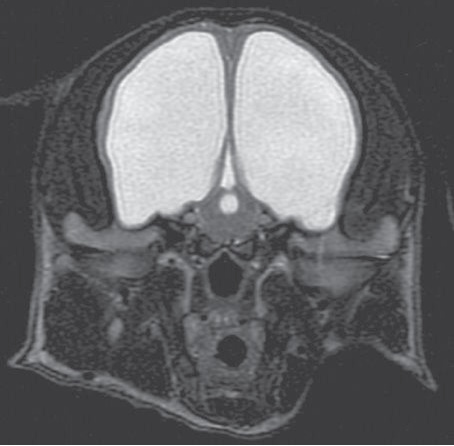

Μαγνητική τομογραφία εγκεφάλου, Τ2 προσανατολισμού, οβελιαία τομή. Απεικονίζεται συμμετρική διάταση των πλαγίων κοιλιών και της τρίτης κοιλίας λόγω συγγενούς υδροκέφαλου.